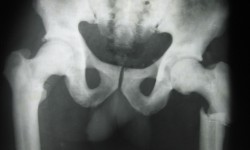

INFANTILE OSTEOPETROSIS By Admin | October 1, 2013 - 4:01 pm | Musculoskeletal, Skeletal Dysplasias Leave a comment FIG. 1 Skull lateral Fig.2 T>L Spine lateral Fig.3 Pelvis A.P with hip and femurs